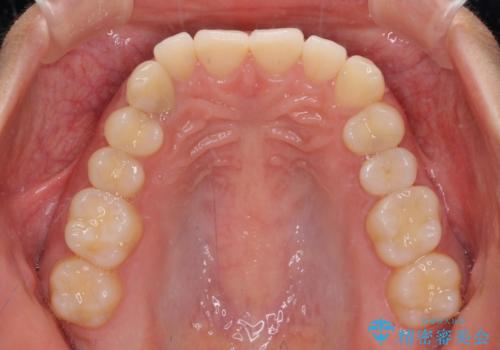

- 下顎の八重歯を気にして来院された患者様です。

マウスピース矯正でもワイヤー矯正でも対応可能であり、マウスピースによる治療を希望されたため、インビザラインを用いることとしました。

下顎前歯にデコボコが集中していたため、顎間ゴムによる後方移動とIPR(歯と歯の間を削ること)により歯列を整えることとしました。

しっかりとマウスピースを装着してくださったおかげで、スムーズに治療を終えることができました。

矯正治療途中で右下奥歯の虫歯治療を近医で行ったようで、既に神経が失活していたと合わせて矯正治療後に補綴治療を行う予定です。